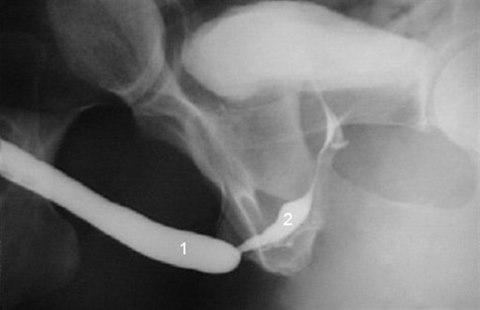

Det er stadig vanligere å behandle uretrastrikturer hos menn med uretroplastikk, men fortsatt er førstevalget vanligvis uretrotomi på tross av at prognosen ved inngrepet er ganske dårlig. Uretroplastikk innebærer at det innsnevrede partiet av uretra fjernes, og det transplanteres slimhinne, f.eks. fra munnslimhinnen, som erstatning. Uretrotomi (DVIU, Direct Visual Internal Urethrotomy) betyr at man insiderer det strikturerte partiet. I Norge er uretroplastikk operasjoner sentralisert til Rikshospitalet.

En retrospektiv studie vurderte data fra 136 menn med tidligere ubehandlet bulbær uretrastriktur for å identifisere risikofaktorer for mislykket behandling ved intern uretrotomi1. Pasientene ble fulgt opp med kontroller hver 4. måned det første året, senere hver 6. måned. Ekskludert fra studien var pasienter med strikturer lengre enn 4 cm, penile og posteriore uretrastrikturer, lichen sclerose, hypospadi eller traume - alle faktorer som er antatt å gi dårligere prognose med endoskopisk behandling.